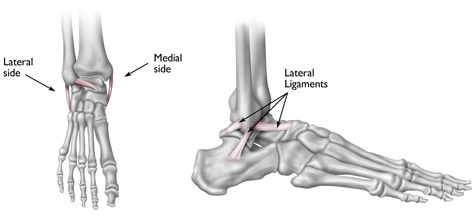

Ligaments are strong, fibrous tissues that connect bones to other bones. The ligaments in the ankle help to keep the bones in proper position and stabilize the joint.

Most sprained ankles occur in the lateral ligaments on the outside of the ankle. Sprains can range from tiny tears in the fibers that make up the ligament to complete tears through the tissue.

An ankle sprain is an injury to one or more of the ligaments that stabilize the ankle.

A twisting force to the lower leg or foot can cause a sprain. The lateral ligaments on the outside of the ankle are injured most frequently.

Reproduced from the Body Almanac @ American Academy of Orthopaedic Surgeons, 2003.